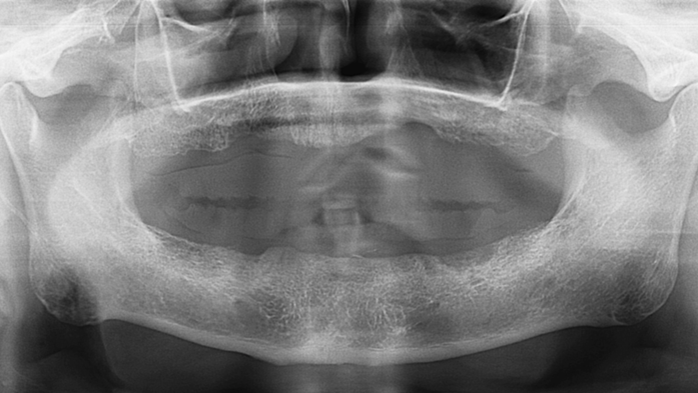

Dr. Sang Tack Lee, edentulous, digital full mouth prosthetics, digital guided surgery, #11, #13, #14, #16, #17, #21, #23, #24, #26, #27, #33, #34, #36, #37, #43, #44, #46, #47, guided surgery, flapless, AnyRidge, R2GATE, Mega ISQ, MEG Torq, MEG Engine, R2GATE Full surgical kit